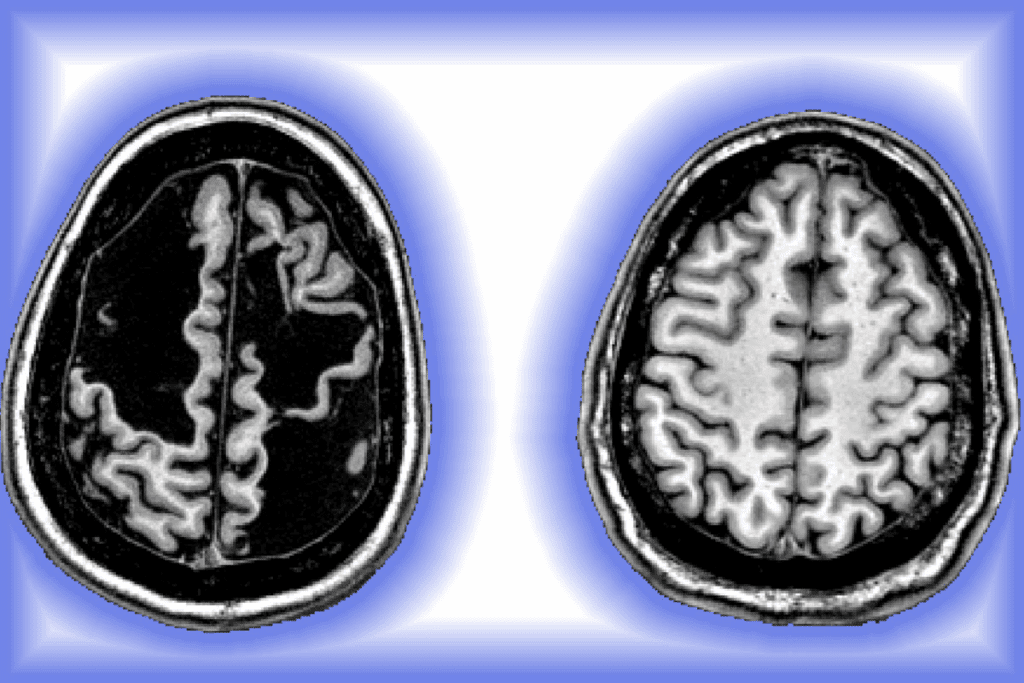

Imaging Studies

Imaging is vital for diagnosing brain metastases. MRI and CT scans are the main tools. MRI is very good at finding brain metastases, thanks to contrast agents.

CT scans are used in emergencies or when MRI is not available. They are quicker but not as good at spotting small metastases as MRI.